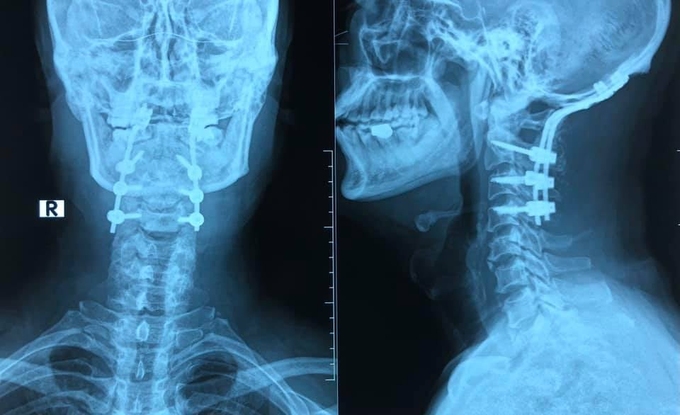

Người đàn ông 55 tuổi ở Hải Phòng nhảy theo tư thế cắm đầu, đụng xuống sàn bể khi bể cạn nước khiến cổ bị gãy.

Sau tai nạn, ông đau chói và hạn chế vận động cột sống cổ, vào bệnh viện được sơ cứu nẹp cố định cột sống cổ, chuyển tới Bệnh viện Trung ương Quân đội 108 tại Hà Nội vào tuần trước.

Các bác sĩ xác định bệnh nhân chấn thương cột sống cổ. Kết quả chụp cắt lớp vi tính cho thấy bệnh nhân bị gãy phức tạp đốt sống C1, cần phải phẫu thuật cố định, làm vững cột sống.

Các bác sĩ khoa Ngoại thần kinh đã tiến hành phẫu thuật cố định chẩm - cổ. Cột sống cổ C2 C3 C4 được cố định bằng vít qua cuống cùng với vít xương chẩm, ghép xương phía sau. Đây là kỹ thuật bắt vít có tác dụng cố định vững chắc nhất về lực.

Phim X-quang chụp sau khi bệnh nhân được cố định, làm vững cột sống. Ảnh: Bác sĩ cung cấp.